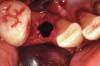

Figure 1  Occlusal view after extraction of tooth No. 27 using Piezosurgery<sup>®</sup> (Piezosurgery Inc, www.piezosurgery.com) and thin-bladed elevators.

Figure 1

Thirty patients were selected on the basis of need for dental extractions with bone preservation and/or augmentation in the socket before the placement of a dental implant. These patients were cleared medically for oral surgical procedures. Preoperative clinical photographs and periapical radiographs were taken. After administration of local anesthesia, full-thickness labial and lingual/palatal flaps were elevated. Minimal soft-tissue manipulation was performed to allow visualization of the entire alveolar crests and debridement of fenestrations and/or dehiscence defects, if present. Elevation of each tooth or retained roots was performed, using periotomes, luxatomes, proximators, root forceps, and any other instruments and procedures as required to extract the tooth with minimal trauma (Figure 1). After extraction and thorough debridement of the socket by mechanical means, clinical photographs were taken. The sites then were grafted with a resorbable β-TCP of small particle size, 150 µm to 500 µm (Cerasorb) (Figure 2). This material has been used and reported in the literature for almost 30 years as a viable bone graft in orthopedic and other surgical specialties. In this study, the granules of β-TCP were mixed thoroughly with blood from the surgical sites and the sockets filled to ideal contours faciolingually and apicocoronally. The grafts and adjacent 3 mm of alveolar bone then were covered with resorbable collagen barriers (BioMend®, www.zimmerdental.com) (Figure 3). The flaps were repositioned and the areas closed with an appropriate number and type of sutures. No attempts were made to obtain primary closure over the exposed barriers. Postoperative radiographs and clinical photographs were taken. Subsequently, sutures were removed at 1 to 2 weeks.